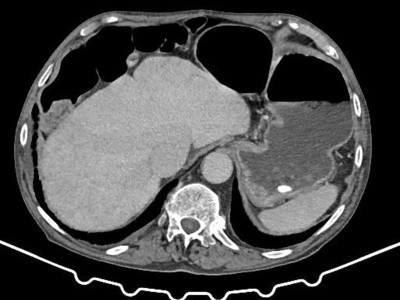

Aktuelle Bedeutung der Radiotherapie bei Plasmozytom und multiplem Myelom

Die Mehrzahl der Personen mit multiplem Myelom benötigt während ihres Krankheitsverlaufs eine lokale Therapie. Diese kann aufgrund von Schmerzen, (drohender) Instabilität oder neurologischer Symptomatik notwendig sein. Dabei kommen insbesondere eine Radiotherapie, operative Eingriffe oder eine Kombination der beiden Methoden zum Einsatz.

Chilaiditi-Syndrom in einer CT-Aufnahme/© Peters F & Ritz J-P/ all rights reserved Springer Medizin Verlag GmbH, Initial potenziell instabile Läsion von BWK 10 bei Multiplem Myelom/© Kaufmann, J., Schmidberger, H. / all rights reserved Springer Medizin Verlag GmbH, Springer Medizin Podcast - Endometriose/© (M) Willer D. et al. / all rights reserved Springer Medizin Verlag GmbH Logo: Springer Medizin Verlag GmbH, Zentrale Lungenembolie/© Springer Verlag Berlin Heidelberg 2015, Volumetrie des Bulbus olfactorius/© Keweloh S.. et al. doi.org/10.1007/s00106-025-01650-z unter CC-BY 4.0, Gebrochener Fuß im Gips/© Aleksandr Kirillov / stock.adobe.com (Symbolbild mit Fotomodell), CT-Pulmonalisangiographie/© Das M et al. doi.org/10.1007/s00117-016-0100-3 unter CC-BY 4.0, Kanüle für Katheterbehandlung/© romaset / stock.adobe.com, Komplexe, offene Fraktur des Ellenbogens vom Grad 2/© Springer Medizin Verlag GmbH, Mann erhält einen CT-Scan /© Mark Kostich / stock.adobe.com (Symbolbild mit Fotomodell), Verschlussazoospermie bei unilateraler zystischer Alteration der Samenblase und kontralateraler Samenblasenagenesie/© Wittler C et al, Indikationen zur konventionellen Bildgebung am Ellenbogen/© Rentschler V et al. / all rights reserved Springer Medizin Verlag GmbH, Person schenkt Bier in Kolben/© Parilov / Stock.adobe.com (Symbolbild mit Fotomodell), Neoadjuvanten Strahlentherapie bei Liposarkom/© Podleska, L.E. et al. / all rights reserved Springer Medizin Verlag GmbH, Frau erhält eine Strahlentherapie/© Mark Kostich / stock.adobe.com (Symbolbild mit Fotomodell), Schaumiges Bronchialsekret bei akutem Lungenödem/© Eichner M. doi.org/10.1007/s00063-025-01258-9 unter CC-BY 4.0, Bildgebung bei akuter Organblutung/© Nadjiri J / all rights reserved Springer Medizin Verlag GmbH, Bildgebung bei Beckenfraktur mit Blutung der A. iliaca interna/© Fink CB et al. / all rights reserved Springer Medizin Verlag GmbH, Traumatische Aortenverletzung/© Maier J et al. / all rights reserved Springer Medizin Verlag GmbH, Oberbauchsonoraphie/© C. Raschka, Muzinöses Prostatakarzinom/© Garzaro JRR et al. / all rights reserved Springer Medizin Verlag GmbH, Intraspinales thorakales Lipom/© Andreas Frank / all rights reserved Springer Medizin Verlag GmbH, Frau bei Strahlentherapie/© (M) Mark Kostich / Stock.adobe.com (Symbolbild mit Fotomodellen), Search Icon, Frau hält sich eine Brustseite nach Mastektomie/© chotiga / Stock.adobe.com (Symbolbild mit Fotomodell), Radiologin richtet Mammographiescreening ein/© LIGHTFIELD STUDIOS / stock.adobe.com (Symbolbild mit Fotomodellen)